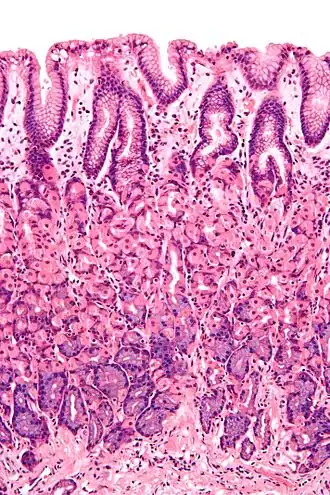

Simple columnar epithelium is a single layer of columnar epithelial cells which are tall and slender with oval-shaped nuclei located in the basal region, attached to the basement membrane. In humans, simple columnar epithelium lines most organs of the digestive tract including the stomach, and intestines. Simple columnar epithelium also lines the uterus.

The shape of the simple columnar epithelium cells are tall and narrow giving a column like appearance. the apical surfaces of the tissue face the lumen of organs while the basal side faces the basement membrane.[1] The nuclei are located closer along the basal side of the cell.[1]

Absorptive columnar epithelium is characterized as having a striated border on its apical side, this border is made up of non-motile microvilli allowing for increase surface area for absorption.[1] These are known as non-ciliated columnar epithelium. Non-ciliated simple columnar epithelium is made up of glandular goblet cells which secrete mucin to form mucus.[1] The rest of the cell is made up of cytoplasm with membrane bound secretory granules which secrete the mucin, and are found towards the apical surface of the cell.[1]

Vertical section of a villus from the dog's small intestine. X 80. (Simple columnar epithelium labelled at right, third from the top.) -

Transverse section of a villus, from the human intestine. X 350.

a. Basement membrane, here somewhat shrunken away from the epithelium.

b. Lacteal.

c. Columnar epithelium.

d. Its striated border.

e. Goblet cells.

f. Leucocytes in epithelium.

f’. Leucocytes below epithelium.

g. Blood vessels.

h. Muscle cells cut across.